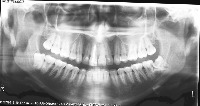

downloadClasses (32)

tooth_11

tooth_12

tooth_13

tooth_14

tooth_15

tooth_16

tooth_17

tooth_18

tooth_21

tooth_22

tooth_23

tooth_24

tooth_25

tooth_26

tooth_27

tooth_28

tooth_31

tooth_32

tooth_33

tooth_34

tooth_35

tooth_36

tooth_37

tooth_38

tooth_41

tooth_42

tooth_43

tooth_44

tooth_45

tooth_46

tooth_47

tooth_48